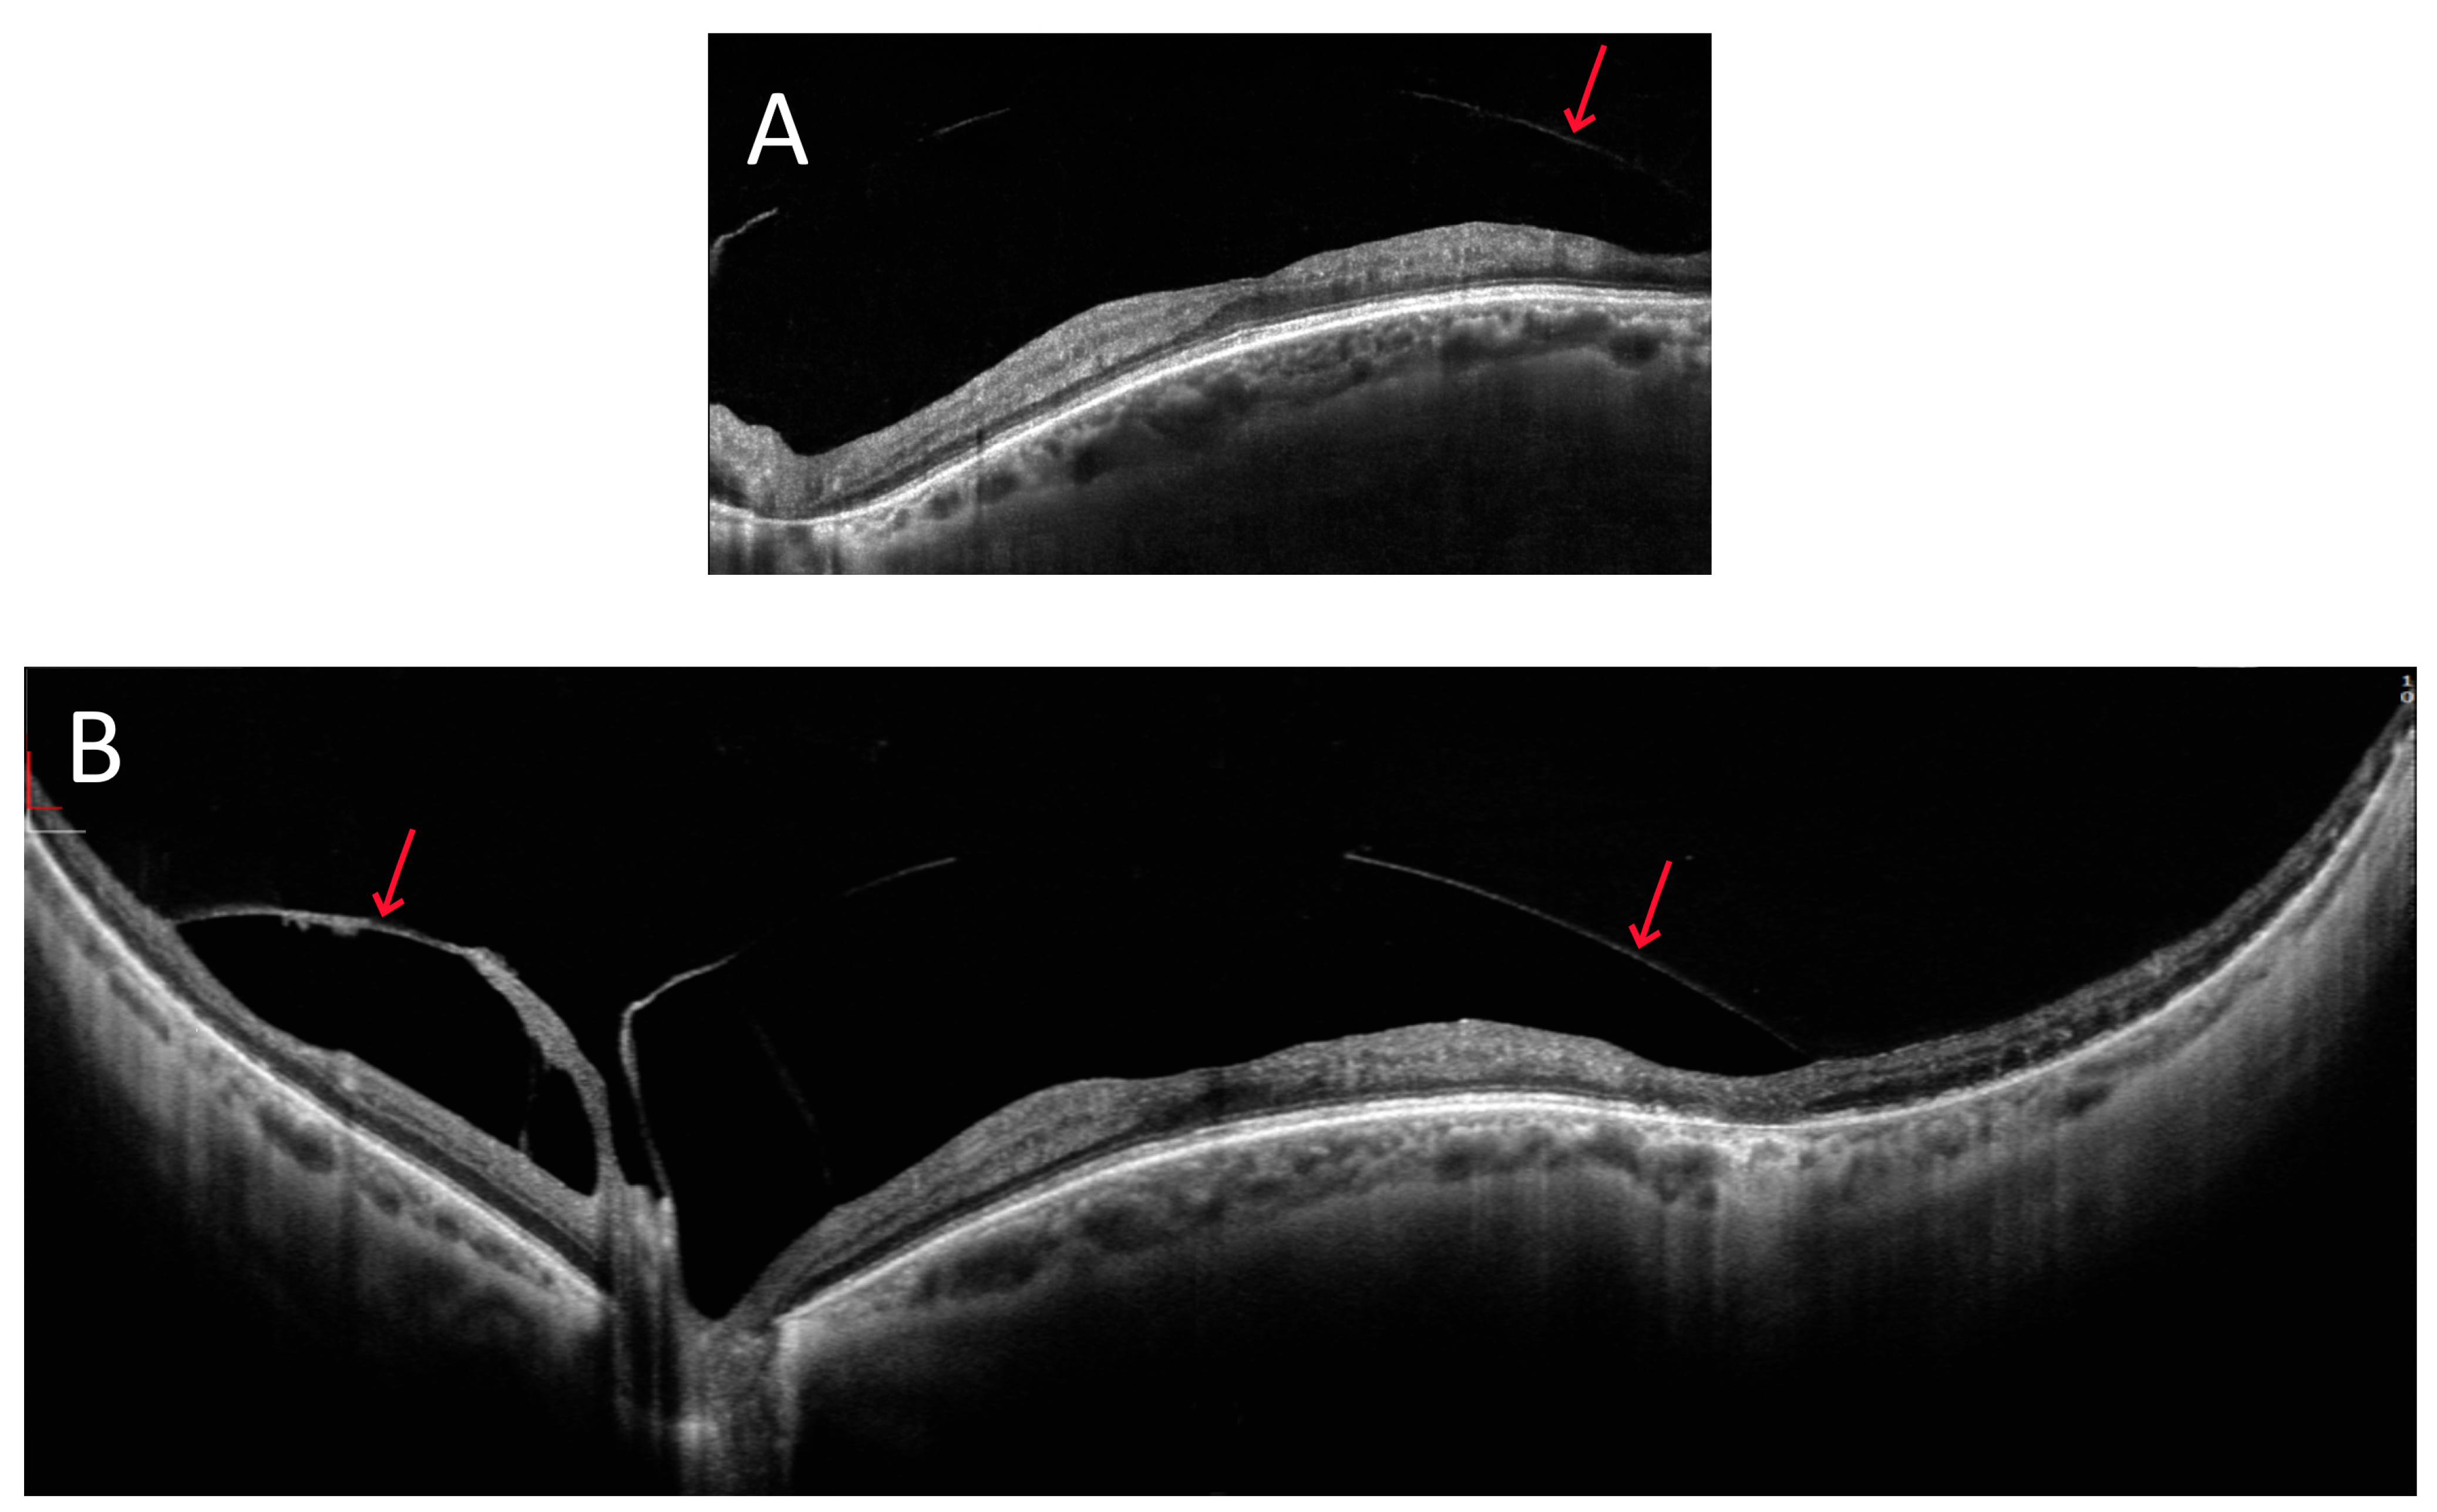

3.1. OCT Measurements

3.3. OCT and Angio-OCT Measurements